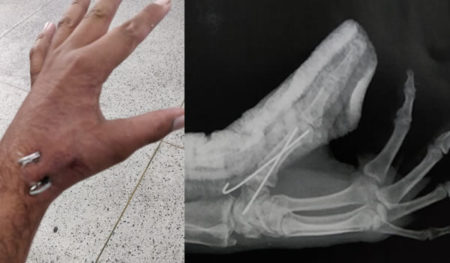

Fratura de Bennett (polegar) em acidente moto x moto